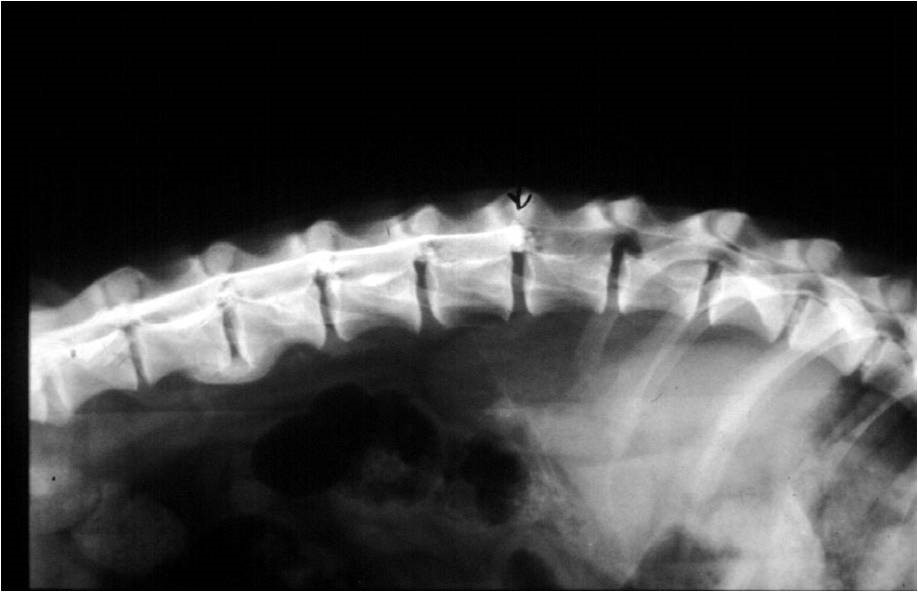

Lumbalis kontraszt stop és

dorsalis szűkület a gerinc csatornában